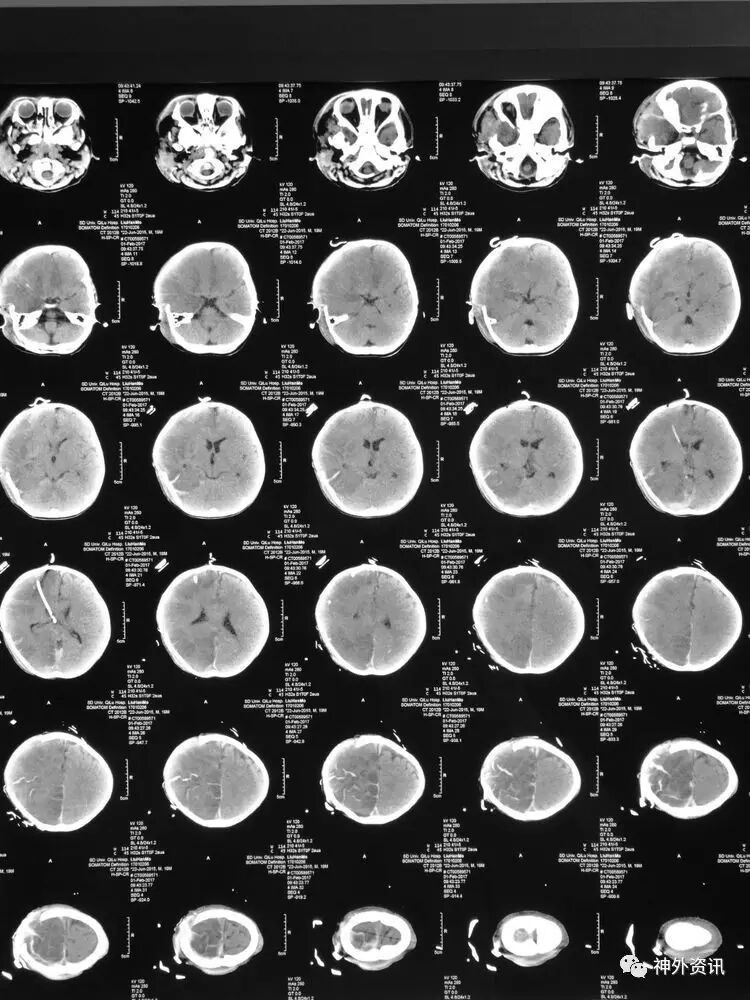

3小时后转至我院急诊科,当时查体:刺痛不睁眼,不发音,刺痛右侧肢体屈曲,右侧瞳孔5mm,对光反应消失,左侧瞳孔0.3cm,对光反应迟钝,立即术前准备并复查CT,结果示右额颞顶枕硬膜下血肿,右侧大脑半球及左侧额叶弥漫性低密度,考虑缺血,中线左移明显,脑沟及环池显示不清:

术后移动CT结果示中线移位较术前减轻,顶枕部蛛网膜下腔出血:

2017.2.1:术后2天复查颅脑CT,结果示中线居中,右侧半球低密度并SAH,左侧半球未见明显异常,左侧脑沟可见显示,双肺少量炎症,不能放松警惕,继续同前治疗。